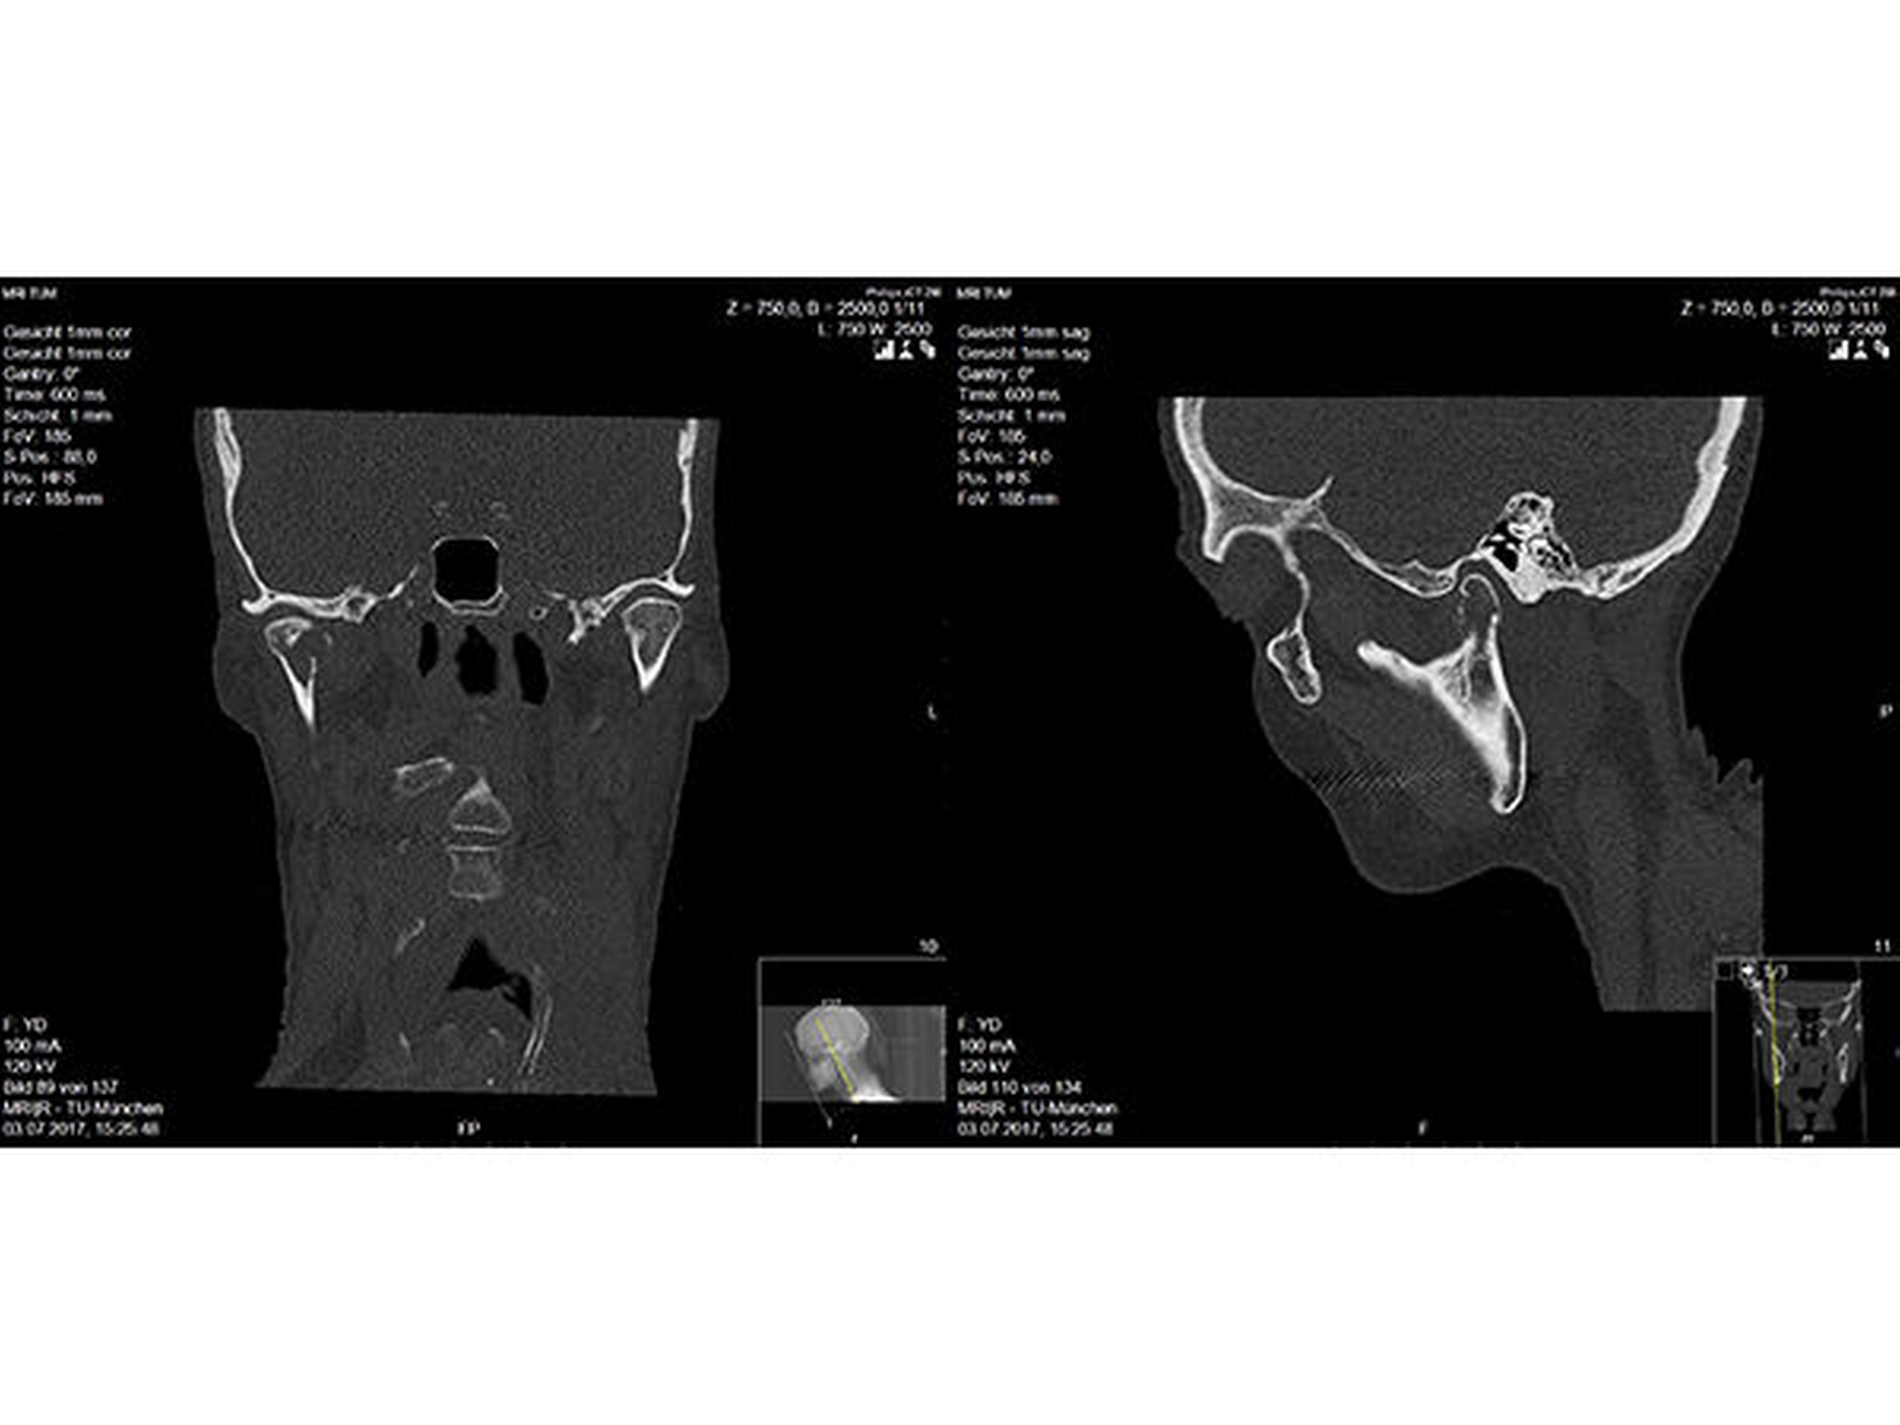

Bei der klinischen Untersuchung beklagte der Patient eine schmerzhaft eingeschränkte Mundöffnung. Darüber hinaus bestanden Frühkontakte im Seitenzahnbereich rechtsseitig sowie ein kontralateral dezent offener Biss. In der zur weiteren Diagnostik durchgeführten Computertomografie (CT) zeigte sich eine pathologische Fraktur des Gelenkfortsatzes auf der rechten Seite sowie eine Osteolyse in Bereich des Kiefergelenks (Abbildung 2). Allgemeinanamnestisch bestand bei dem Patienten ein hepatisch und pulmonal metastasiertes Kolonkarzinom.